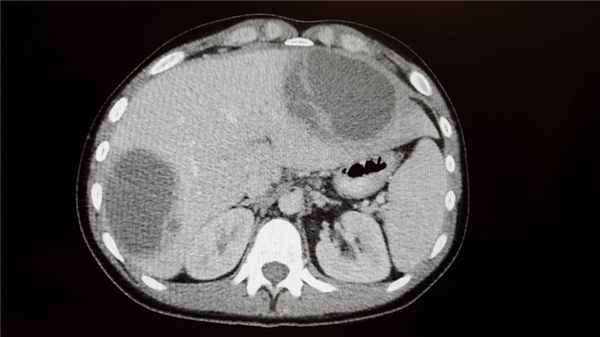

Абсцессы могут располагаться в любой части брюшной полости и забрюшинного пространства. Чаще они развиваются после хирургических вмешательств, травм, инфекционно-воспалительных заболеваний органов брюшной полости, особенно сопровождающихся развитием перитонита и перфорации. Проявления включают общую слабость, лихорадку, боль в животе. Диагноз ставится на основе КТ. Лечение подразумевает хирургическое или чрескожное дренирование. Дополнительно назначают антибиотики.

КТ органов брюшной полости

При подозрении на абсцесс методом выбора является КТ брюшной полости и таза с пероральным контрастированием. Другие способы визуализации также могут выявить некоторые изменения; при обзорной рентгенографии брюшной полости может определяться газ в полости абсцесса, смещение соседних органов, мягкотканное образование, соответствующее абсцессу, либо исчезновение тени подвздошно-поясничной мышцы. При расположении абсцессов вблизи диафрагмы могут наблюдаться изменения со стороны грудной клетки, такие как плевральный выпот, высокое стояние и снижение подвижности купола диафрагмы, инфильтрация в нижней доле, ателектаз на стороне поражения.